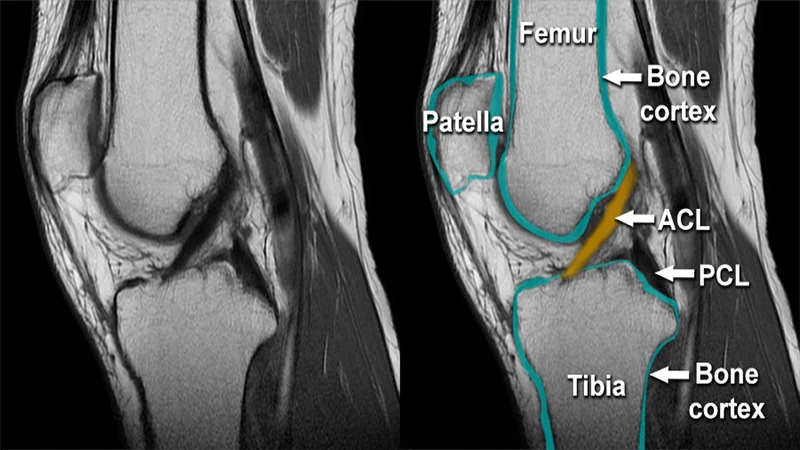

- Musculoskeletal (MSK): MRI is used to diagnose injuries to ligaments, tendons, cartilage, and muscles, such as a torn ACL in the knee or a rotator cuff tear in the shoulder.